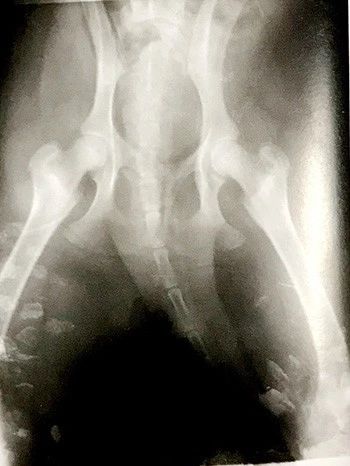

图9 佝楼病

5月龄狼犬缺钙,骨皮质变薄

【诊断】根据年龄和饲喂食物中维生素D、钙、磷情况,生长迟缓、异嗜癖、出牙期延长及骨骼变形等特征一般不难诊断。必要时可利用X射线检查,发现骨质密度降低、长骨末端“羊毛状”特点。另外,生化检查,血清钙和磷含量降低(血清钙低于9mg/dL,血磷低于2.5mg/dL),碱性磷酸酶活性显著升高,有助于本病的诊断。